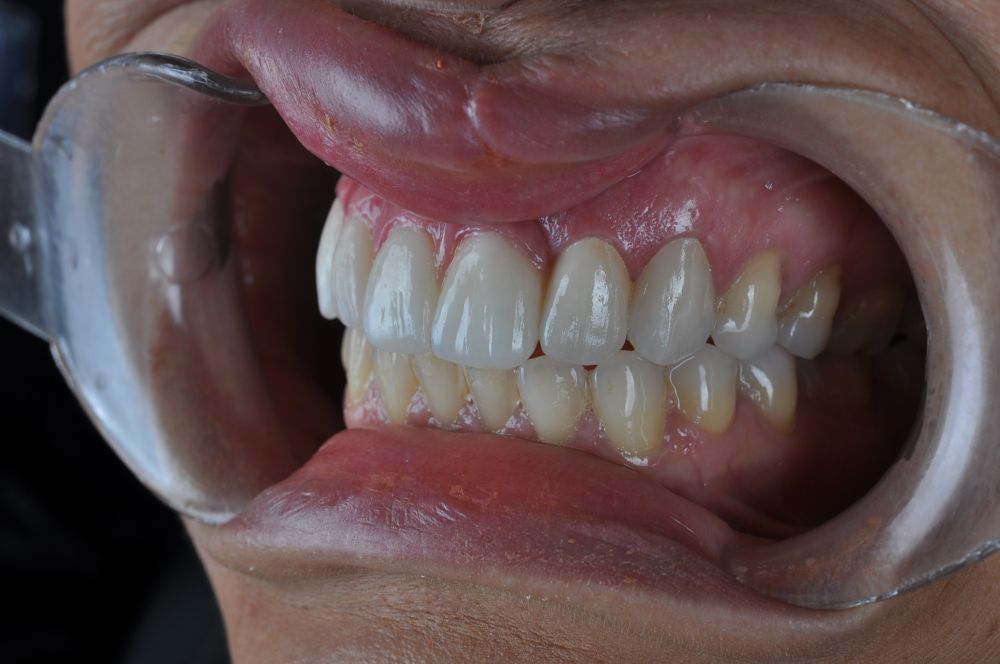

Para la fabricación de las estructuras, se eligió el óxido de zirconio monolítico como material restaurador sobre interfases metálicas en el puente implantosoportado, y coronas de óxido de zirconio monolítico en los dientes tallados previamente (1.7, 1.6, 2.2 y 2.3). Se tomaron impresiones de cubeta abierta con silicona de adición pesada y fluida (Zhermack Elite HD, Gmbh). Se realizó una prueba de pasividad analógica y el resto del proceso se confeccionó de manera digital, por lo que se hicieron pruebas estéticas de dientes impresas en 3D sobre interfases metálicas, para hacer todos los ajustes de función y estética previos al fresado del zirconio monolítico (Figuras 11, 12 y 13).

El día de la colocación de las estructuras, se arenó el interior de las coronas dentosoportadas con óxido de aluminio de 50 m y fueron cementadas con cemento de resina Multilink Ò. El puente implantosoportado se atornilló al torque indicado (20Nw) (Figuras 14, 15, 16 y 17).

Las impresiones analógicas y el posterior flujo digital permitieron una correcta planificación protésica. Las estructuras definitivas, confeccionadas en óxido de zirconio monolítico sobre interfases metálicas de titanio, mostraron una adecuada adaptación pasiva tanto clínica como radiográficamente. La prueba estética permitió ajustes oclusales y funcionales mínimos, optimizando el resultado final.

En enero de 2021, el puente implantosoportado fue atornillado con un torque controlado (20 Nw), y las coronas dentosoportadas cementadas con éxito. La paciente refirió una notable mejoría en la función masticatoria, fonación y estética facial, manifestando un alto grado de satisfacción.